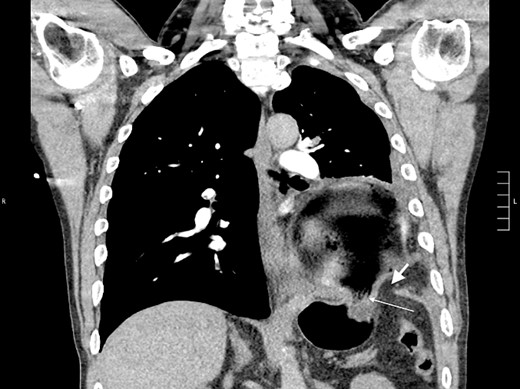

Thirty-seven days after the initial visit, the patient returned to the emergency department with burning epigastric pain that radiated to the left upper chest and hematemesis. Vital signs revealed tachycardia and hypertension. A comprehensive physical exam was significant for decreased breath sounds at the left base and tenderness in the left upper quadrant without signs of peritonitis. Pertinent laboratory findings showed leukocytosis with a left shift and thrombocytosis. A chest X-ray showed a significant portion of the gastric body in the left hemithorax (Fig. 1). A pulmonary CT angiogram found segmental and subsegmental pulmonary emboli in both lungs with no evidence of right heart strain and a left pleural effusion. A left diaphragmatic hernia with the “dangling diaphragm” sign can be seen on the sagittal view (Fig. 2). The coronal view shows discontinuity of the diaphragm and the “collar” sign (Fig. 3); the axial view shows the “dependent viscera” sign and thoracic fluid abutting abdominal viscera (Fig. 4).

Coronal CT showing the gastric body herniating through diaphragmatic defect, discontinuity of the diaphragm (thick arrow), and the “collar” sign (thin arrow).